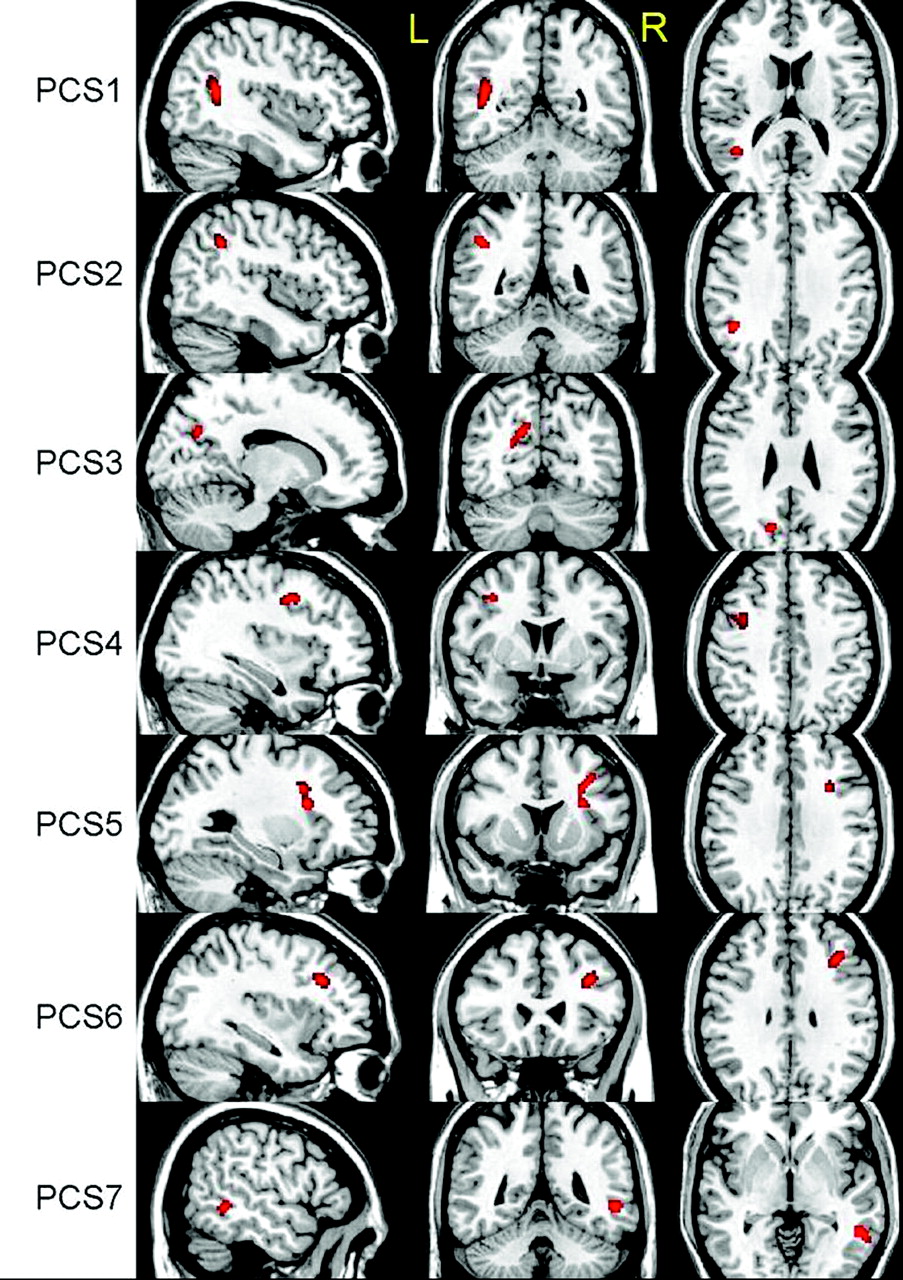

VBA revealed 6 regions with significant decreases in ADC, t(18) = 3.6, P < .001, by using a cluster size of >50 voxels (Fig 1). As expected, most regions identified were located in WM structures with the exception of the left thalamus. No region was found to have a significant increase in ADC by using the same thresholds. The linear regression analysis between ADC and RPCSQ indicated a significant negative relation in 7 regions, t(18) = 3.3, P < .002, by using a cluster size of >40 voxels (Fig 2), which were again located predominantly in the WM. Again, no significant regions between ADC increase and RPCSQ were identified, consistent with the results of the group analysis.

Three-plane views of 6 regions (GRP 1–6) identified by ADC-GRP analysis, superimposed on a structural image.

Three-plane views of 7 regions (PCS 1–7) identified by ADC-RPCSQ analysis, superimposed on a structural image.

In the original mTBI study by Wilde et al,17 decreased ADC and increased FA were found within the midsagittal fibers traversing the CC in patients with acute mTBI relative to controls. As expected, VBA revealed similarly decreased ADC in regions with projections through the CC but also demonstrated several additional areas of decreased ADC (Fig 1). Even with diverse causes of injury, it appears that there are areas of commonality of both WM and GM regions in mTBI. As with more severe injury, there appear to be diffuse changes in WM regions with known susceptibility to shear-strain forces, such as the superior frontal longitudinal fasciculus and the cingulate bundle. In addition, change in association regions such as the thalamus may not be surprising, given the complex connectivity to other regions. Findings suggest that the effects of mTBI are indeed widespread, consistent with the distribution of DTI abnormalities observed during the chronic phase following mTBI.4–6,34 Given that the participants were all scanned within 6 days of injury, it is plausible that some of these acute abnormalities may evolve into more chronic WM changes. Longitudinal DTI investigation of patients with mTBI is underway to evaluate this further.